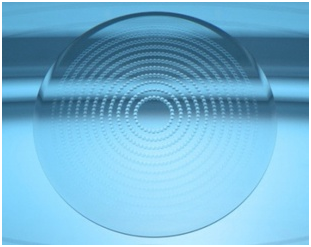

Линзы ZEISS MyoCare

В линзах при близорукости ZEISS MyoCare используются специальные микроструктуры в периферической зоне линзы. Центральная часть, предназначенная для коррекции зрения вдаль, окружена практически невидимыми кольцами, которые обеспечивают коррекцию зрения. Такая методика предотвращает быстрое удлинение глаза и замедляет прогрессирование миопии.

Чтобы обеспечить детям чёткое зрение во всех направлениях, специалисты компании Zeiss оптимизировали заднюю поверхность выпускаемых линз. Она рассчитывается и обрабатывается в процессе производства по технологии FreeForm. Это также предотвращает появление нежелательного гиперметропического дефокуса при всех положениях взгляда.